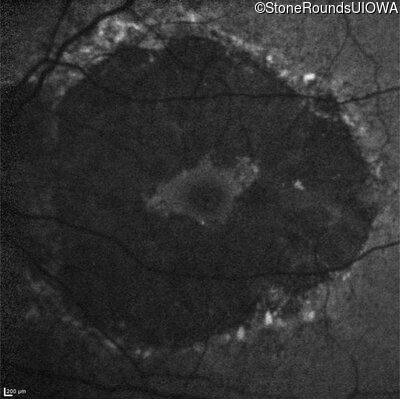

Infrared Fundus Photograph - Left - 20/20 -1

Exemplar